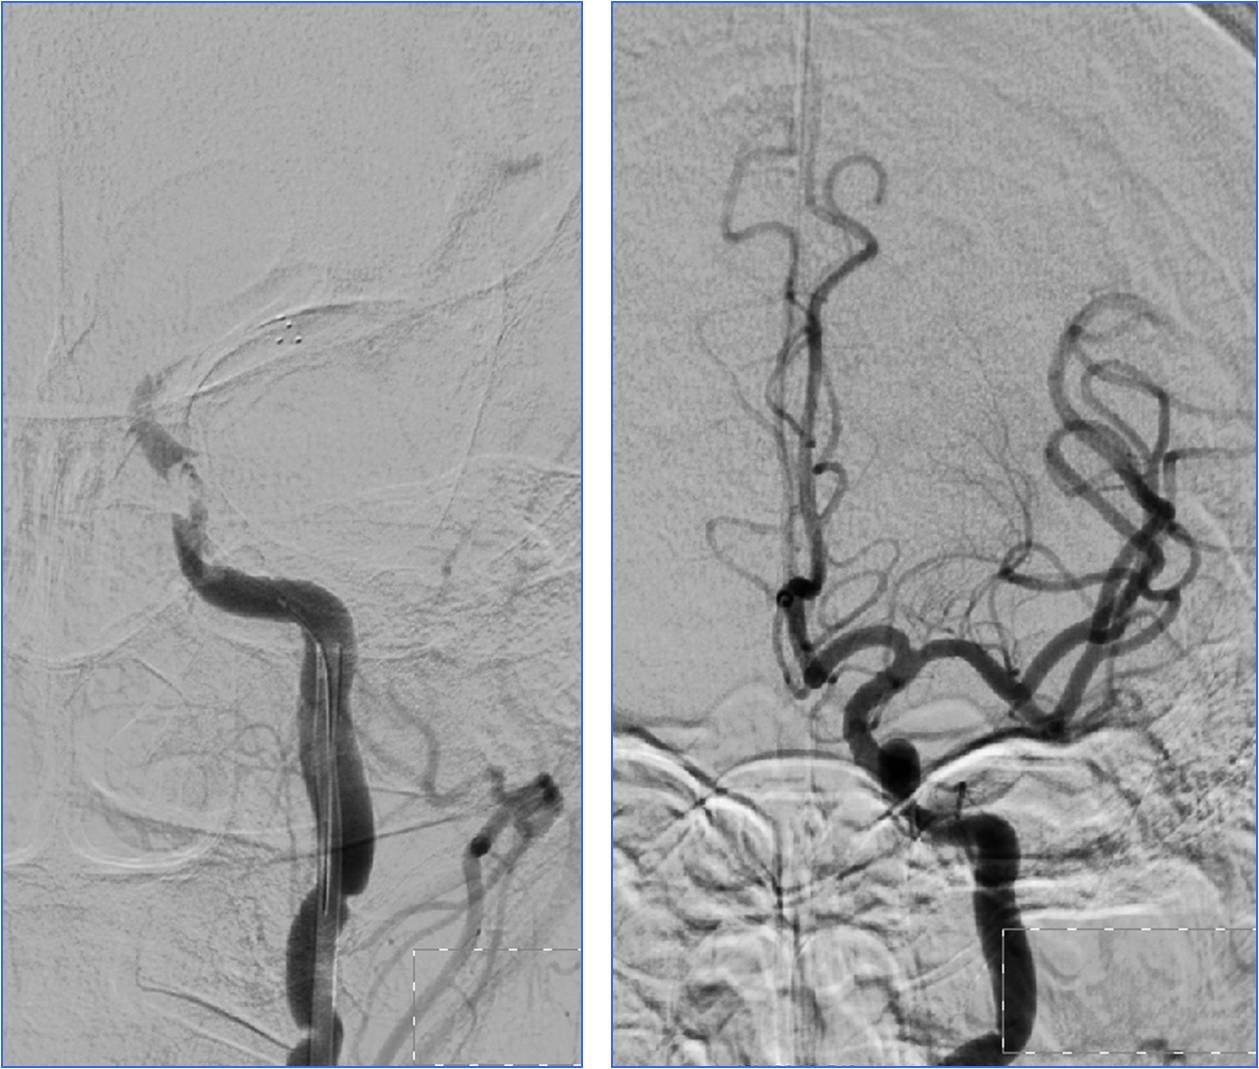

Case8 风心病、心脏瓣膜病脑栓塞

》58岁,女性,既往风心病、房颤、心脏瓣膜病

》因“活动后心慌胸闷5年”于心外科住院,拟行心脏瓣膜置换术

》12:30出现言语不清、左侧肢体无力,NIHSS 18分

》13:00完成头CT检查

》请神经内科会诊,转科 Ø14:00行股动脉穿刺

》15:15结束手术

》16天后出院,NIHSS 2分

再发脑栓塞

》6月份行二尖瓣、主动脉瓣置换术

》7:50出现言语不清、左侧肢体无力,NIHSS 25分

》9:10完成头CT检查

》9:35行股动脉穿刺

》10:05结束手术

》10天后出院,NIHSS 3分

》原因:服用华法林不达标,INR 1.31